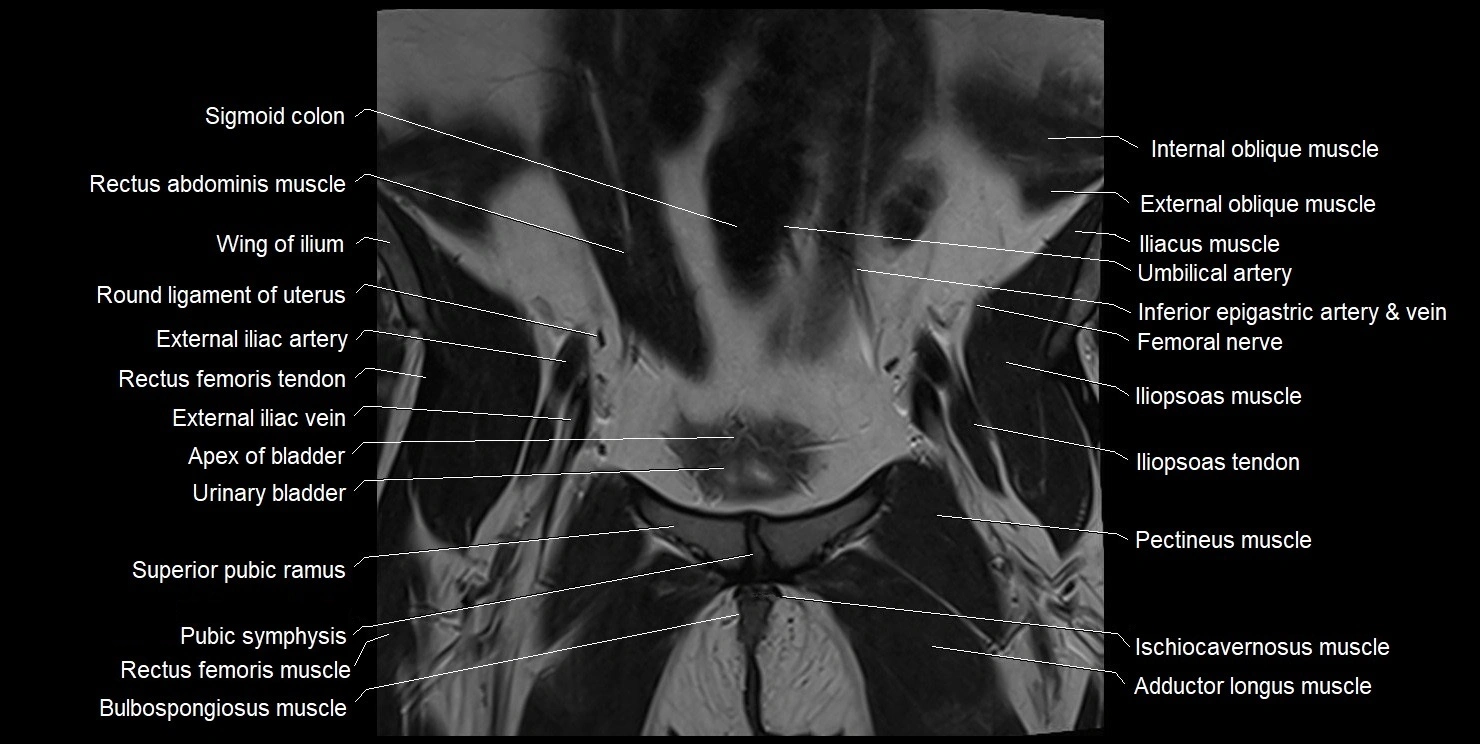

- Adductor longus muscle

- Apex of urinary bladder

- Bulbospongiosus muscle (Female)

- External iliac artery

- External iliac vein

- Femoral nerve

- Iliopsoas muscle

- Iliopsoas tendon

- Ischiocavernosus muscle (Female)

- Pectineus muscle

- Pubic symphysis

- Rectus femoris muscle

- Rectus femoris tendon (Proximal tendon of rectus femoris)

- Round ligament of uterus

- Sigmoid colon

- Superior pubic ramus

- Urinary bladder